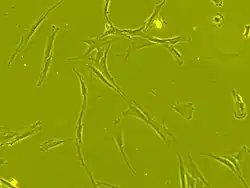

Human bone marrow derived mesenchymal stem cells seen under phase contrast microscope at 63-times magnification)

Scientists are investigating various avenues for treatment of spinal cord injury. Therapeutic research is focused on two main areas: neuroprotection and neuroregeneration.[78] The former seeks to prevent the harm that occurs from secondary injury in the minutes to weeks following the insult, and the latter aims to reconnect the broken circuits in the spinal cord to allow function to return.[78] Neuroprotective drugs target secondary injury effects including inflammation, damage by free radicals, excitotoxicity (neuronal damage by excessive glutamate signaling), and apoptosis (cell suicide).[78] Several potentially neuroprotective agents that target pathways like these are under investigation in human clinical trials.[78]

Stem cell transplantation is an important avenue for SCI research: the goal is to replace lost spinal cord cells, allow reconnection in broken neural circuits by regrowing axons, and to create an environment in the tissues that is favorable to growth.[78] A key avenue of SCI research is research on stem cells, which can differentiate into other types of cells—including those lost after SCI.[78] Types of cells being researched for use in SCI include embryonic stem cells, neural stem cells, mesenchymal stem cells, olfactory ensheathing cells, Schwann cells, activated macrophages, and induced pluripotent stem cells.[164] Hundreds of stem cell studies have been done in humans, with promising but inconclusive results.[151] An ongoing Phase 2 trial in 2016 presented data[165] showing that after 90 days, 2 out of 4 subjects had already improved two motor levels and had thus already achieved its endpoint of 2/5 patients improving two levels within 6–12 months. Six-month data was expected in January 2017.[166]